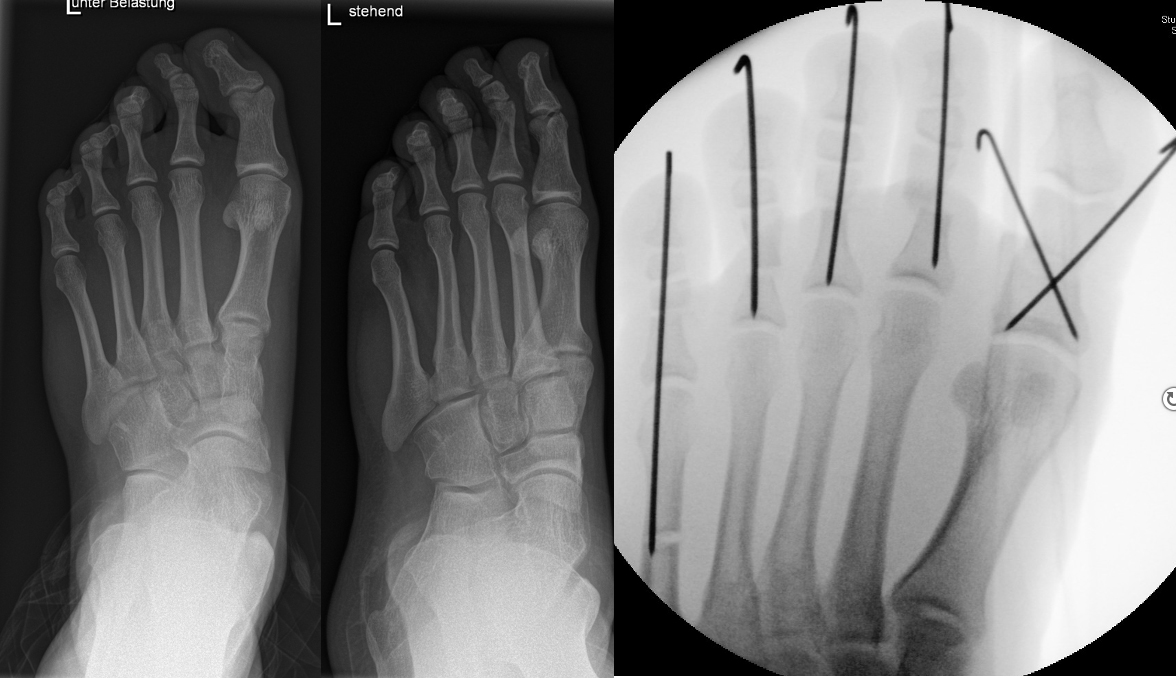

Knick-Senk-Platt-Fuß Korrektur mit dem Canalis Tarsi Spacer

In der Korrektur des schmerzhaften, aber flexiblen Knick-Senk-Fußes oder Plattfußes ist die Schraubenarthrorise mit einem Sinus tarsi oder besser bezeichnet als Canalis tarsi Spacer und alternativ mit einer Calcaneus-Stopp-Schraube seit vielen Jahren ein etabliertes Verfahren und führt zu einer kompletten Korrektur von flexiblen Knick- und Plattfuß-Fehlstellungen (Abb. 7). Die nötige Schnittlänge über dem Sinus tarsi beträgt für beide Verfahren 1 cm.

Abb. 7 a-e: Knick-Senk-Fuß prä- und postoperative Situation (a-b), ventrale und dorsale Ansicht (c-d). Laterale Ansicht des Hautschnittes über dem Sinus tarsi (e).

Zum Lesen der Bildbeschreibung und zur Vollansicht bitte die Bilder anklicken. Bilder: A. Helmers.